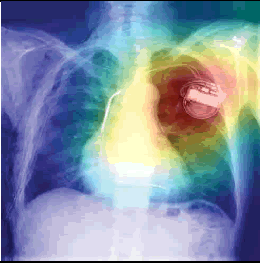

우리에게 굉장히 적은 데이터들이 주어졌을 때, supervised learning을 적용한다면 흔히 overfitting 문제가 발생할 것입니다. 예를 들어, 우리에게 아래와 같은 Chest X-Ray 폐렴 데이터만 갖고 있다고 해보겠습니다.

이미지 출처:https://www.openaccessjournals.com/articles/advanced-neural-network-solution-for-detection-of-lung-pathology-and-foreign-body-on-chest-plain-radiographs-13104.html

그림 출처:https://www.openaccessjournals.com/articles/advanced-neural-network-solution-for-detection-of-lung-pathology-and-foreign-body-on-chest-plain-radiographs-13104.html

의사들이 보는 폐렴 증상은 분명 폐주위의 섬유화에 주목하겠지만, 딥러닝의 경우는 CAM(=Class Activation Map)을 통해 살펴보면 엉뚱한데주목하는 경향이 있습니다. 아래와 같이 엉뚱한 곳을 보는 이유폐렴 관련 데이터는 저런 부분들만 살펴봐도 분류가 가능했기 때문일 수 있습니다. 즉, 정답의 이유는 상관없이 "학습 데이터의 정답만 맞추면 된다"는 식인 것이죠.

하지만, 저런 artifacts와 같은 요소들이 없는 폐렴 데이터가 들어오면 곧 바로 틀려버립니다. 즉, supervsied learning 방식을 사용한 CNN적은 수 의 폐렴 데이터로 학습하게 되면, 폐렴 CXR 이미지를 제대로 representation 해줄 수 없게 된다고 이야기 할 수 있습니다.